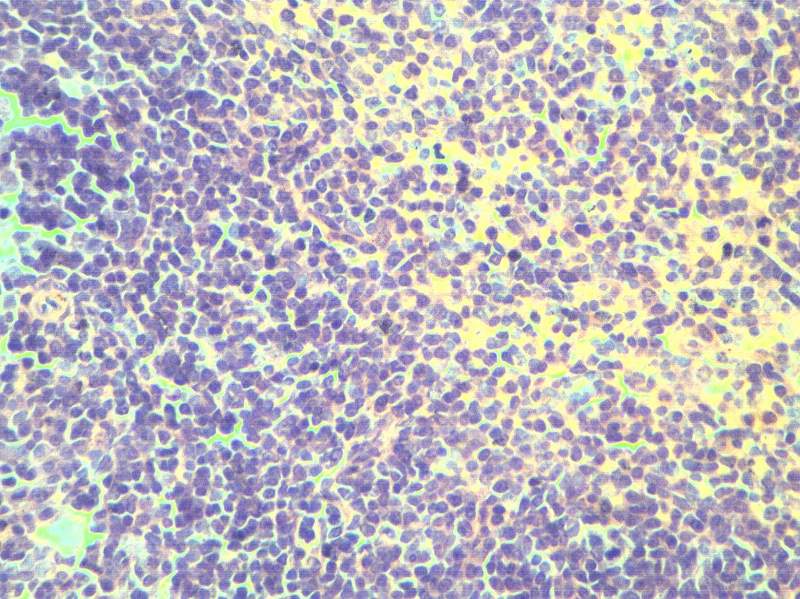

СÊóÆ¢ÔàºÍÖ×Áö×éÖ¯HEȾɫ½á¹ûÃèÊö

×î½üÔÚ×öÒ©ÀíʵÑ飬¶ÔСÊóµÄÆ¢ÔàºÍÖ×Áö×éÖ¯½øÐÐÁËHEȾɫ£¬¿àÓÚ¶ÔÆ¢Ôà½á¹¹²»Á˽ⲻ»á¶Ô½á¹û½øÐзÖÎö£¬ÌØÏò´ó¼ÒÇóÖú£¬Íò·Ö¸Ðл Æ¢ÔàµÍ±¶ Æ¢Ôà¸ß±¶ Æ¢ÔàµÍ±¶ Æ¢Ôà¸ß±¶ Ö×Áö×éÖ¯µÍ±¶ Ö×Áö×éÖ¯¸ß±¶ |